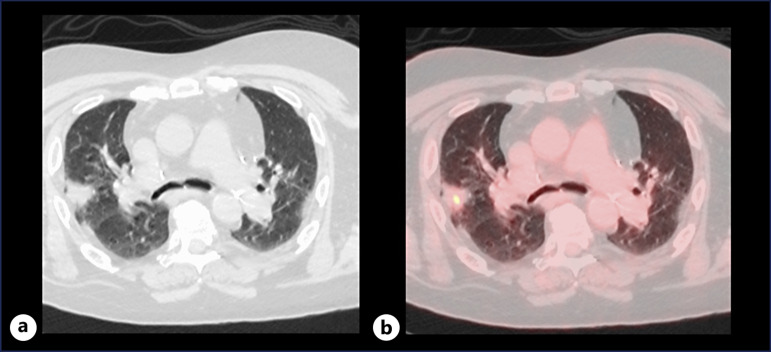

Case presentation: A 50-year-old patient underwent double lung transplantation (LTx) in July 2018 for progressive fibrosing interstitial lung disease (ILD). IMA was unexpectedly found in the explant lungs. Pre-transplant PET-CT scans suggested inflammatory ILD without malignancy. Endobronchial ultrasound-guided transbronchial fine needle aspiration of the enlarged mediastinal lymph nodes demonstrated no evidence of malignancy. Post-transplant pathology confirmed stage IVA IMA with a KRAS G12D mutation. After 3 years, recurrent IMA was detected. The asymptomatic patient remains under close surveillance with stable lung function, and tailored treatment will be considered if progression occurs.